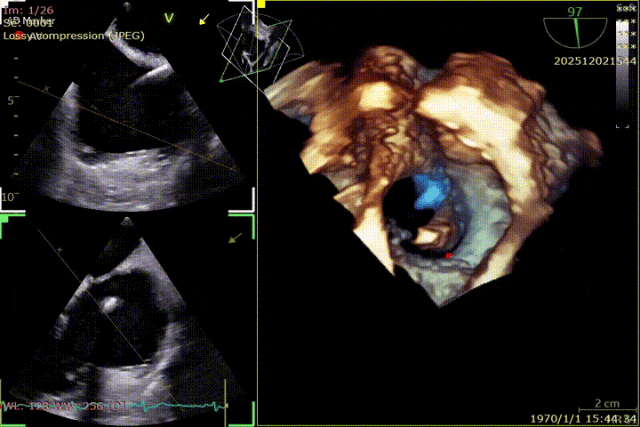

During the procedure, close collaboration was maintained with Dr. Yang Yan (anesthesiologist, Department of Anesthesiology) and Dr. Niu Ming (echocardiography specialist, team of Director Zhai Hong, Department of Cardiac Ultrasound). Guided by transesophageal echocardiography and assisted by DSA imaging, the tricuspid annular structure and regurgitation jet direction were precisely assessed. Ultimately, two 12T K-Clip® devices were successfully implanted. Immediate postoperative echocardiographic evaluation showed a significant reduction in tricuspid regurgitation from 4+ preoperatively to 1+, with a marked decrease in annular area. The surgical outcome was satisfactory.

Echocardiographic: Severe tricuspid regurgitation (grade 4+), with the regurgitant jet mainly located at the posteroseptal and central regions. No significant dilatation of the tricuspid annulus is observed. Mild myxomatous degeneration of the tricuspid leaflets is present, showing Barlow-like morphology, with leaflet prolapse of 3.7 mm in height.

CT : The tricuspid annulus has a circumference of 139 mm and an area of 1423 mm². The overall distance between the RCA and TA was greater than 3 mm in both systole and diastole. The right coronary artery is slightly deviated toward the atrial side, indicating a low risk of coronary artery injury during the procedure.

Surgical Outcome

Preoperative Regurgitation: 4+

Annulus Area: 11.3 cm²

Postoperative Regurgitation: 1+

Annulus Area: 4.9 cm²